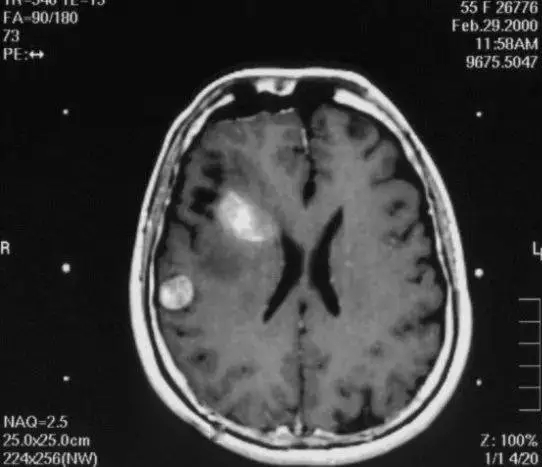

伽马刀又称立体定向伽马射线放射治疗,是融立体定向技术和放射技术于一体,以治疗颅内疾病为主的立体定向放射外科治疗设备。其原理是将钴-60发出的伽马射线几何聚焦,集中射于病灶,一次性致死性的摧毁靶点内的组织,射线经过人体正常组织几乎无伤害,并且剂量锐减,相比其他治疗照射范围与正常组织间界限非常明显,边缘如刀割一样,人们形象称之为“伽玛刀”。

伽玛刀的适应症:

1. 头部良性肿瘤:脑膜瘤、垂体瘤、听神经瘤、脑血管畸形、三叉神经痛等;

2. 头部恶性肿瘤:脑胶质瘤、脑转移瘤、淋巴瘤等。

伽玛刀治疗的优点:

1. 全过程清醒,疗程短,一般只需要一天的时间;

2. 采用旋转聚焦的手段,可以做到靶区剂量高,而周围正常组织受量较低,保护了正常的脑组织;

3. 属于微创治疗手段,只需要四个定位螺钉于头部固定即可;

4. 治疗条件受年龄、身体状况及心脏病、高血压、糖尿病等疾病的影响较小;

5. 拒绝手术的患者,或有手术禁忌的患者也可以耐受伽马刀治疗。